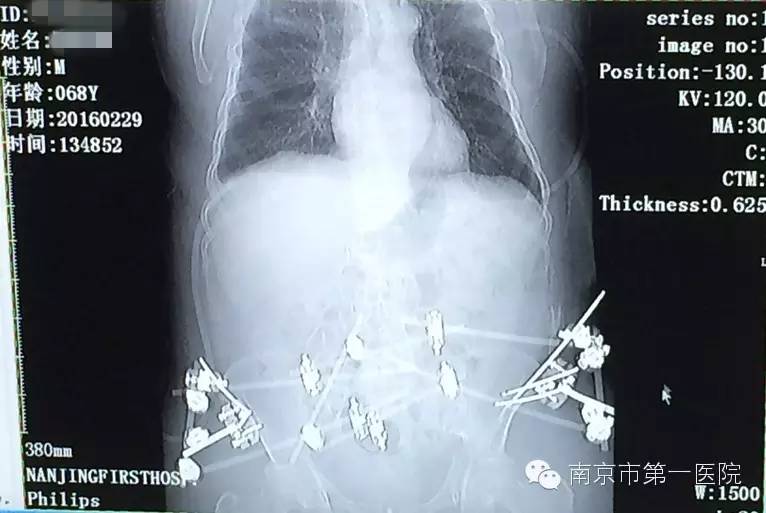

1月25日,因为车祸造成老张骨盆内有血管损伤,在他病情相对稳定后,医生准备对其造影介入手术,安置防血栓滤网,防止肺血栓再次发生。手术过程中,他又出现21日的症状,心肺复苏抢救10分钟后,终于再次将他从死亡线上拉了回来。

“老张盆骨的血管有损伤,血管壁就会很毛糙,失血性休克会导致血液流动速度缓慢,容易形成血栓,这也是老张出现危险的主要原因。心肺复苏后,随后对他进行了血栓滤网的放置,后来再也没有出现类似情况了。”郑曙云还表示,经过一系列的抢救治疗,老张已经脱离危险,情况良好,以后还能像正常人一样自理生活。